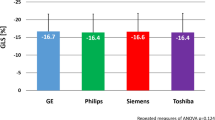

Inter-vendor agreement

Figure 4 shows box and whisker-plots to illustrate the range of strain values with regard to the different sites and the significance level of the differences, as calculated from the Bland-Altman analysis. The range of GLS-measurements was wider than of GCS-measurements. Differences in strain values were significant when comparing site I against either site II or III. Table 2 and Fig. 5 display the results of the Bland-Altman analysis. Inter-vendor agreement was good between all sites, shown by small biases (0.01–1.88% strain), but the limits of agreement (LOA) reflected a possible inconsistency regarding individual patients. Biases and limits of agreement were significant when comparing site I against either site II or III.

To our knowledge, no previous data on inter-vendor agreement of a CMR-technique to determine strain exists. Nevertheless, the influence of different ultrasound systems on 2D- and 3D-STE has been reported previously [7, 29,30,31]. As in our study, differences in STE-strain measurements between the different vendors were significant [7, 29, 30]. However, the bias between different ultrasound systems was similar or higher (0.1–3.7 [7], 1.1–7.0 [30], 1–1.55% [31]) than the bias between magnetic resonance scanners determined in our study group of fifteen volunteers (0.01–1.88%), with limits of agreement of a similar magnitude. The bias in our cohort of healthy volunteers was significant between site I and II or III. Moreover, the limits of agreement indicate that in some individuals the difference in strain values could be considerably higher than the bias. We believe that this study demonstrates the importance of further exploring inter-vendor agreement in larger cohorts to validate these results and to determine the agreement related to different scanners in patients. Our results indicate that it might possibly be helpful to implement scanner-related normal values and that one should be aware of this possible bias and limits of agreement when comparing strain results acquired at different scanners. This should also play a role when designing classifications based on strain, which determine diagnostic procedures and therapeutic decisions for patients.

Our results suggest that an average bias of 0.01% to 1.88% strain (< 1.24% for GLS and < 1.88% for GCS) should be taken into account when comparing fSENC results of healthy individuals acquired using different scanners. This implies that a strain difference of below 2% on average may represent normal variability in the measurement and not necessarily a decrease or increase in myocardial function, if scanning is performed using different scanners. The limits of agreement indicate that strain results from different scanners should not be used totally interchangeably. Larger studies are needed for further validation in order to facilitate the planning and comparison of multi-center studies, which are needed for standardization of strain measurements and to determine inter-vendor agreement in patients. Furthermore, technical differences between different scanners and imaging sequences should be assessed.